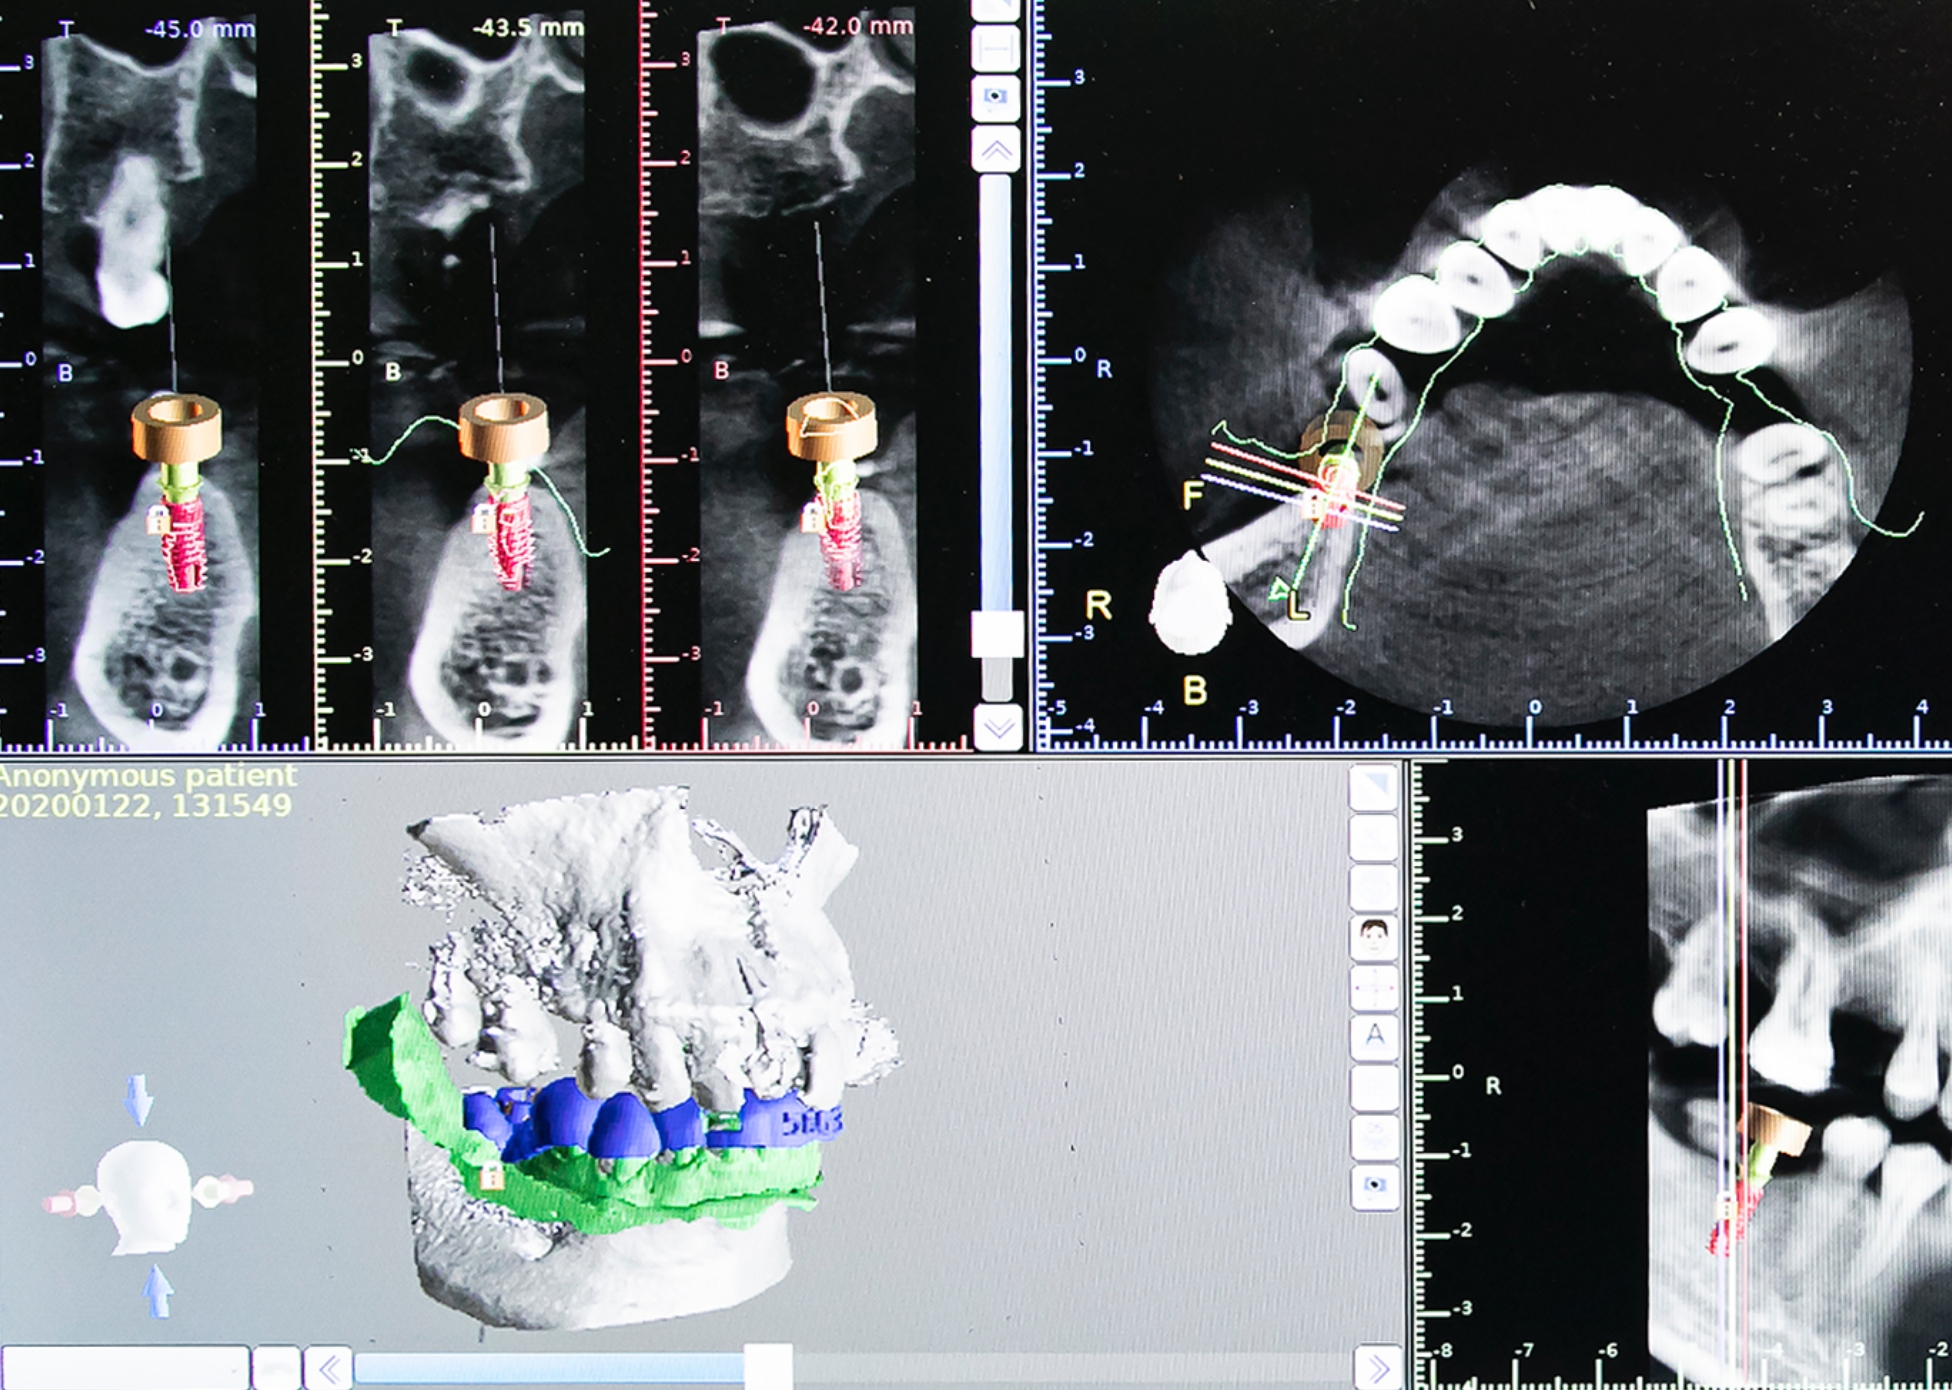

手術したその日に噛める!1Dayインプラント

ALL-on-4 オールオンフォー

歯が1本も残っていない場合(無歯顎)、入れ歯で困っている方必見の治療法です!症例実績も豊富な安心で確実な治療法です。

下顎4本、上顎4~6本のインプラントによりブリッジを固定し、手術したその日に噛む機能面と審美面が回復するまったく新しいタイプの術式です。これまで、歯を全て失ってしまった方のインプラント治療は、上下それぞれ8~10本のインプラントが必要でした。また、治療期間はとても長く、治療費も非常に高額でした。All-on-4なら治療コストを低減でき、治療期間も短縮する事ができます。